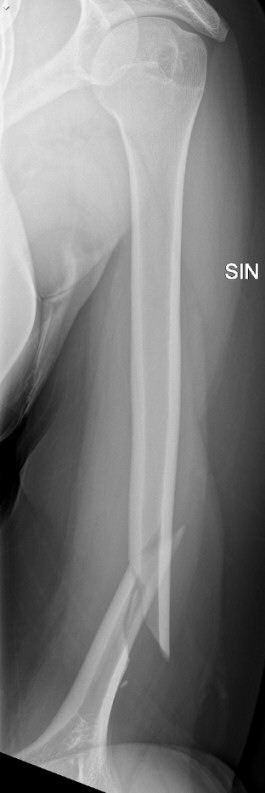

Exempel på humerusfraktur som behandlats icke-kirurgiskt, röntgenbilder efter 19, 40 resp. 71 dagar